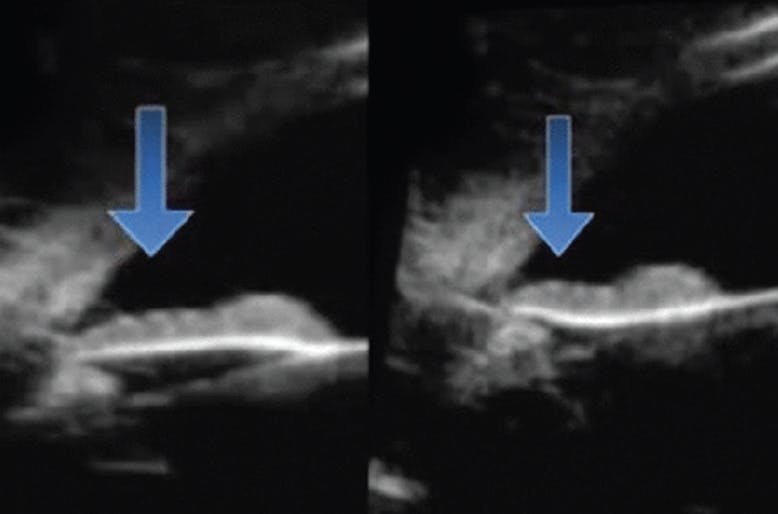

Figure 1. The arrow indicates posterior bowing of the iris with accommodation and increased iris-lens-zonule rubbing.

Enlargement of the lens is one of the most identifiable worldwide causes of pigment liberation and angle closure that contribute to glaucoma.1 In this age-related disorder, the lens enlarges, leading to increased iridolenticular and iridozonular contact. This is exacerbated by posterior bowing of the iris during accommodation (Figure 1).2